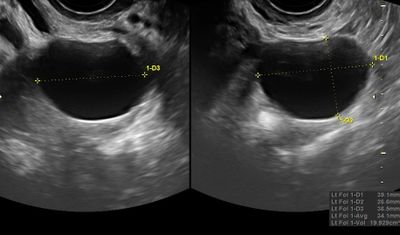

Typical benign ovarian cyst